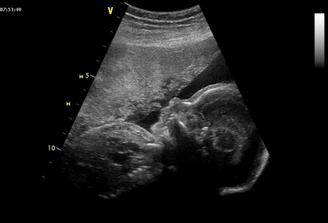

Tak se na nás snad už štěstí konečně usmálo a na IVF už nepůjdeme....... Měli jsme těsně před stimulkou na 2.IVF a čekali na mrchu. Místo toho jsme 15.3.2009 objevili naše krásné //. 17.03.2009 bylo na UTZ vidět plodové vejce, cca 2,7mm, další kontrola 31.3.2009. Tam už byl vidět náš bobeček, 6,3mm veliký a srdíčko mu bilo jako o závod. Dostali jsme krásné fotečky a jsme moc šťastní. Tak konečně je 23.4.2009 a jsme i s taťkou na dalším UTZ, jsme 9+6. Paní doktorka z nás měla velkou radost, říkala, že tak mrskající se miminko už dlouho neviděla. Velikostí odpovídáme úplně na den, máme už těhu průkajdu a dneska jsem se objednala na časný genet. skr. k MUDr. Břešťákovi. Termín porodu je 20.11.2009 a manža má narozky 24.11. 2009. No a já je mám zítra, takže super dnešní dárek. Tak dneska 11.5. 2009 jsem byla u zubaře pro razítko do těhu průkajdy a už ho mám. Další den 12.5.2009 jsme byli u mé praktické paní doktorky, natočila mi EKG a dala nám razítko do těhu průkajdy. Dneska 14.5.2009 jsme byli s manžílkem na genetickém screeningu. Pan doktor a sestřička byli moc hodní. Sestřička mi nabrala krev, vůbec jsem nezaznamenala, že je po odběru, je moc šikovná. Výsledky budou do 14-ti dnů. Pan doktor nám ukázal miminko v celé své kráse, jsme obříci, máme skoro 8 cm, NT 1,8 mm. Dle pana doktora jsme o 6 dnů větší a odpovídáme 13+5 (dle MS 12+6), tak nám upravil termín porodu na 14.11.2009. Slyšeli jsme tlukot srdíčka a bylo to nádherné, 160 úderů /min.. Pan doktor nám dal fotečky na CD, tak jsme moc šťastní. Jelikož nám pan doktor posunul termín porodu o týden dříve, tak jsme se byli 19.05.2009 zaregistrovat k porodu do FN Motol. Dneska 21.05.2009 jsme byli na kontrole a dostali jsme fotečky obličejíčka našeho mimíska. Je to celý tatínek. Mimísek na nás koukal a pěkně skotačil, paní doktorka nám ukázala jak má právě nožičku u hlavičky. Na den dětí 01.06.2009 jsme se dozvěděli, že výsledky screeningu jsou v pořádku. Jsme moc rádi. Dne 04.06.2009 jsem si volala na výsledky krevních triple testů a sestřička mi sdělila, že jsou v pořádku. Jsme s taťkou moc šťastní. Tak dneska 11.06.2009 jsme byli na kontrole u naší paní doktorky a s taťkou jsme byli zvědaví, jestli se nám už ukáže holčička nebo chlapeček. Paní doktorka se moc snažila, říkala, že by to viděla na holčičku, ale že opravdu spíše tipuje, protože miminko nechtělo roztáhnout nožičky. Tak uvidíme, jestli nám to řekne pan doktor na velkém UTZ, kam se objednáme. Bylo vidět, jak si miminko podpírá ručičkou bradičku a paní doktroka nám udělala nějaké fotečky. Jsme s tatínkem moc rádi, že se má miminko fajn. Dneska končíme 4. měsíc. Po měsíci -7.7.2009 jsme konečně zase viděli naše miminko. Paní doktorka nám ukázala močový měchýř, srdíčko, žaludek. Miminko se mrskalo, dokonce nám zamávalo. Paní doktorka nám řekla, že na 90% čekáme holčičku!

14.7.2009 jsme byli s taťkou na velkém UTZ (22+3) u pana MUDr. Břešťáka. Pan doktor byl fajn, ukázal nám miminka srdíčko, frekvenci srdíčka, tok krve do srdíčka a do aorty, játra, ledviny, močový měchýř..., dokonce i základy zoubků. Změřil všechny orgány a tělíčko a byl moc spokojený, vše je tak, jak má být. Nakonec nám potvrdil, že čekáme HOLČIČKU! Mrskala s sebou , chvíli trvalo, než pan doktor mohl změřit srdeční frekvenci. Vážíme 492g. Jsme s tatínkem moc šťastní, že je malá v pořádku. Dneska objednáme kočárek casualplay s4. Tak dneska 26.7.2009 jsme se byli s tatínkem podívat na naši holčičku na 4D UTZ. Udělali nám dvd a fotečku. Malá se nejdřív moc nechtěla ukazovat, schovávala se a točila se k nám zády. Pak si ale dala říct a krásně se nám ukázala. Je moc hezká, je to celý tatínek. Má jeho nosánek, pusinku, bradičku. Byla to sranda, zívla si a dala si nožičku k pusince, pak se pošťourala v oušku. A je to malá čertice, mrskala s sebou pěkně. Když jsme si jí doma prohlíželi na dvd, tak taťkovi dala pořádný kopanec, až vyskočil. 4D UTZ je fajn a my jsme spokojení. 4.8.2009 jsem byla na testu na cukrovce, ble. Ale nebylo to tak hrozný a máme splněno. 5.8.2009 jsme volali na vysledky jak nám cukrovka dopadla a výsledky jsou v pořádku, jupíí. Hnedka jsem to oslavila 2x koblihou a 2x croisantem. 11.8.2009 jsme byli na kontrole, malinká je v pořádku a je otočená hlavičkou dolů. Paní doktorka říkala, že je šikovná a že si myslí, že už takhle zůstane. Tak konečně uběhl měsíc a kousek a my se jdeme s taťkou podívat na naši holčičku. Paní doktorka říkala, že bude Michalku měřit, jsme totiž 32. týden. Paní doktorka malou změřila, odpovídáme úplně na den 31+3 a vážíme 1445g. Paní doktorka říkala, že Michalka je krásně proporční miminko, úplně podle tabulek a že by měla při porodu mít okolo 3500g. Michalka je moc šikovná, je stále hlavičkou dolů. Jupííí, jsme s tatínkem moc rádi. 01.10.2009 jsme byli u paní doktorky na další kontrole a Michalka se má dobře, krásně jí tlouklo srdíčko a je stále hlavičkou dolů, jupíí. Dostali jsme formulář na mateřskou a od 09.10.2009 na ní nastupujeme, jůůů, toto letí. Tak dneska je 13.10.2009 a byli jsme na poslední kontrole u naší paní doktorky, malá se má dobře, hlavičkou je stále dolů a váží 2300g, je to pěkný cvalík. Máme s tatínkem radost. CS máme 2. Už budeme chodit na kontroly do porodnici v Motole, kam se musíme objednat. 27.10.2009 jsem byla poprvé v poradně v Motole, paní doktorka nás vyšetřila, CS asi 4, pak jsme poslouchaly srdíčko naší malé princezny, zrovna cvičila spartakiádu. Kontrola v pořádku. Další kontrola bude i s monitorem, tak se moc těšíme. Dnes 03.11.2009 jsem byla v poradně v Motole, poprvé nám dělali monitor a malá se tak vrtěla, až mi sklouzla sonda a musela jsem si jí tam pak držet. Malá měla výsledky monitoru v pořádku, tak jsme moc s tatínkem rádi. Paní doktorka mě dnes nevyšetřovala, až zase na příští kontrole. Dneska je 10.11.2009, náš další den, kdy jsme se vydali do poradny. Natočili nám monitor, výsledky monitoru jsou v pořádku a paní doktorka mě i vyšetřila. CS 4, čípek zkrácený, měkký, hlavičkou je hezky nastavená. Je to naše malá šikulka a už se na ní s tatínkem móóc těšíme!!!